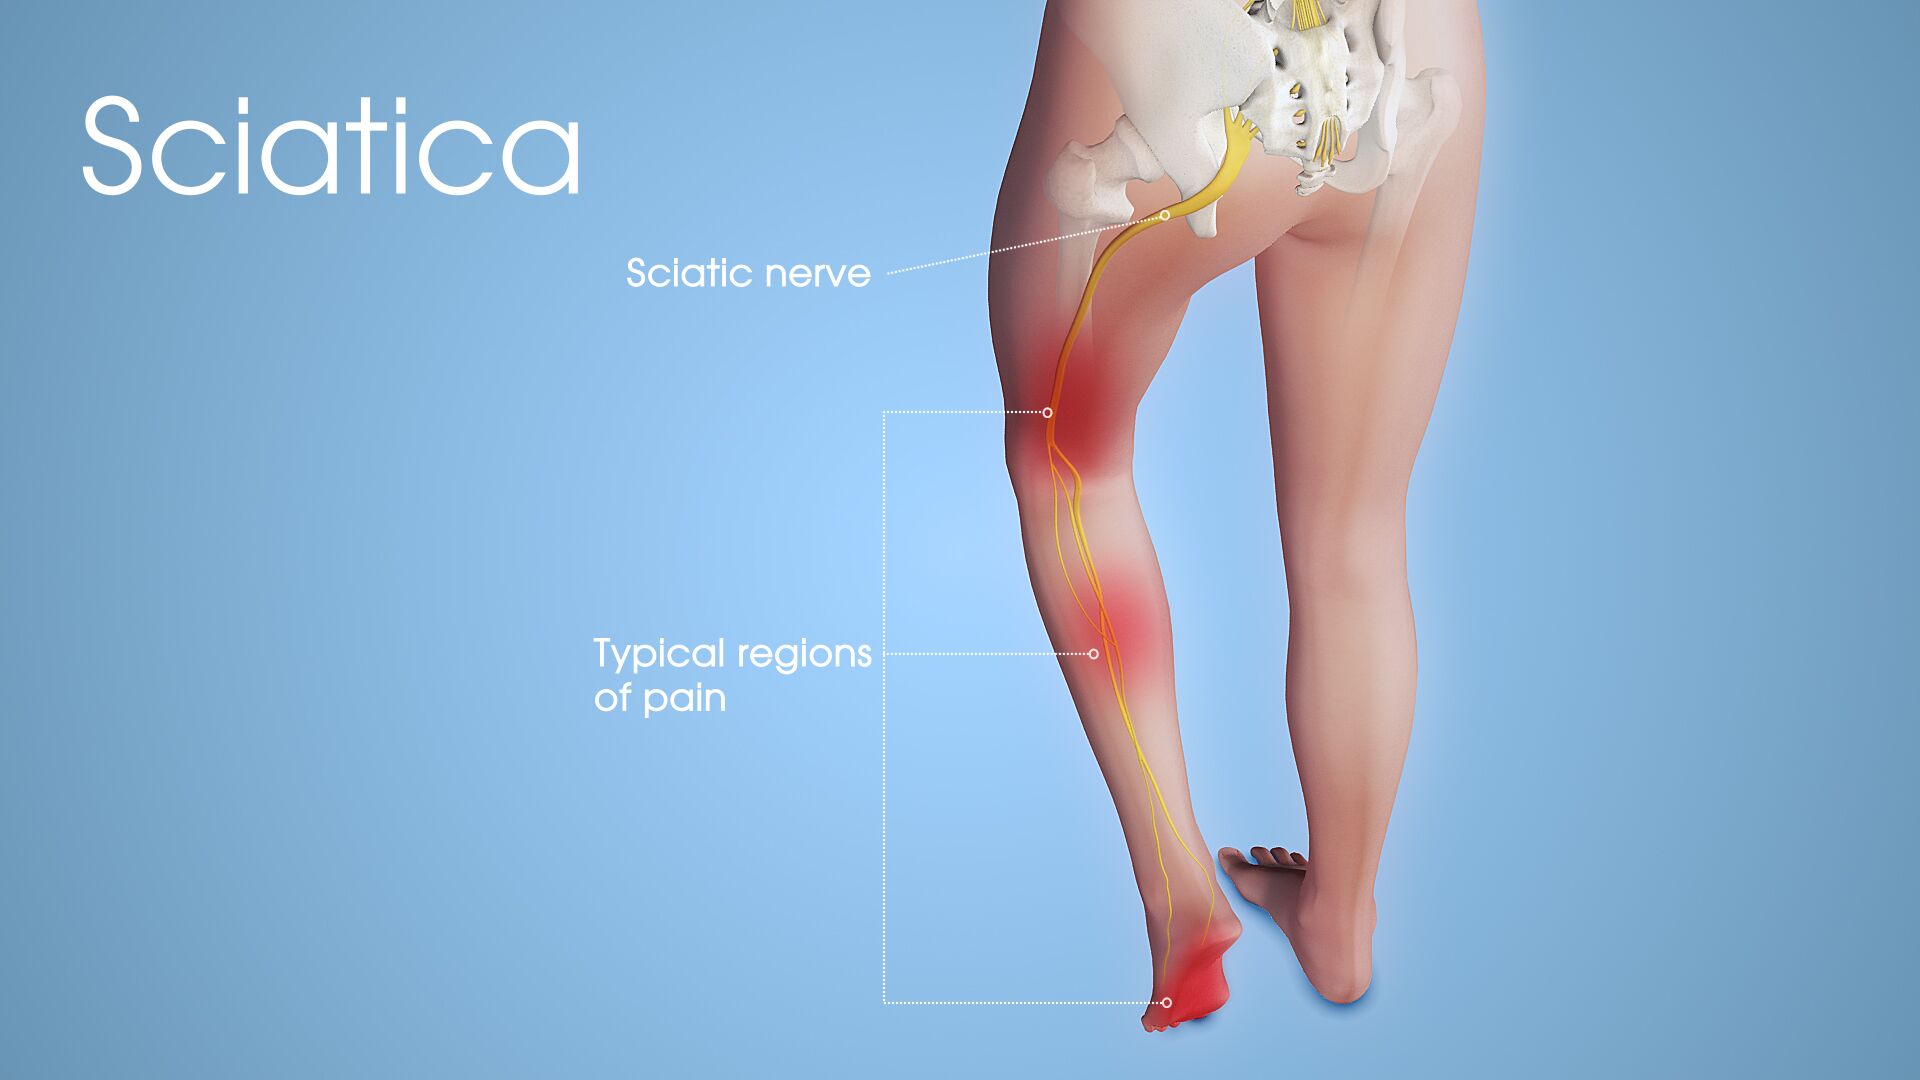

What causes a burning sensation in the lower back?

Lumbar spine (lower back): Sciatica /Radiculopathy frequently results from a herniated disc in the lower back. Pressure on one or several nerves that contribute to the sciatic nerve can cause pain, burning, tingling and numbness that radiates from the buttock into the leg and sometimes into the foot.